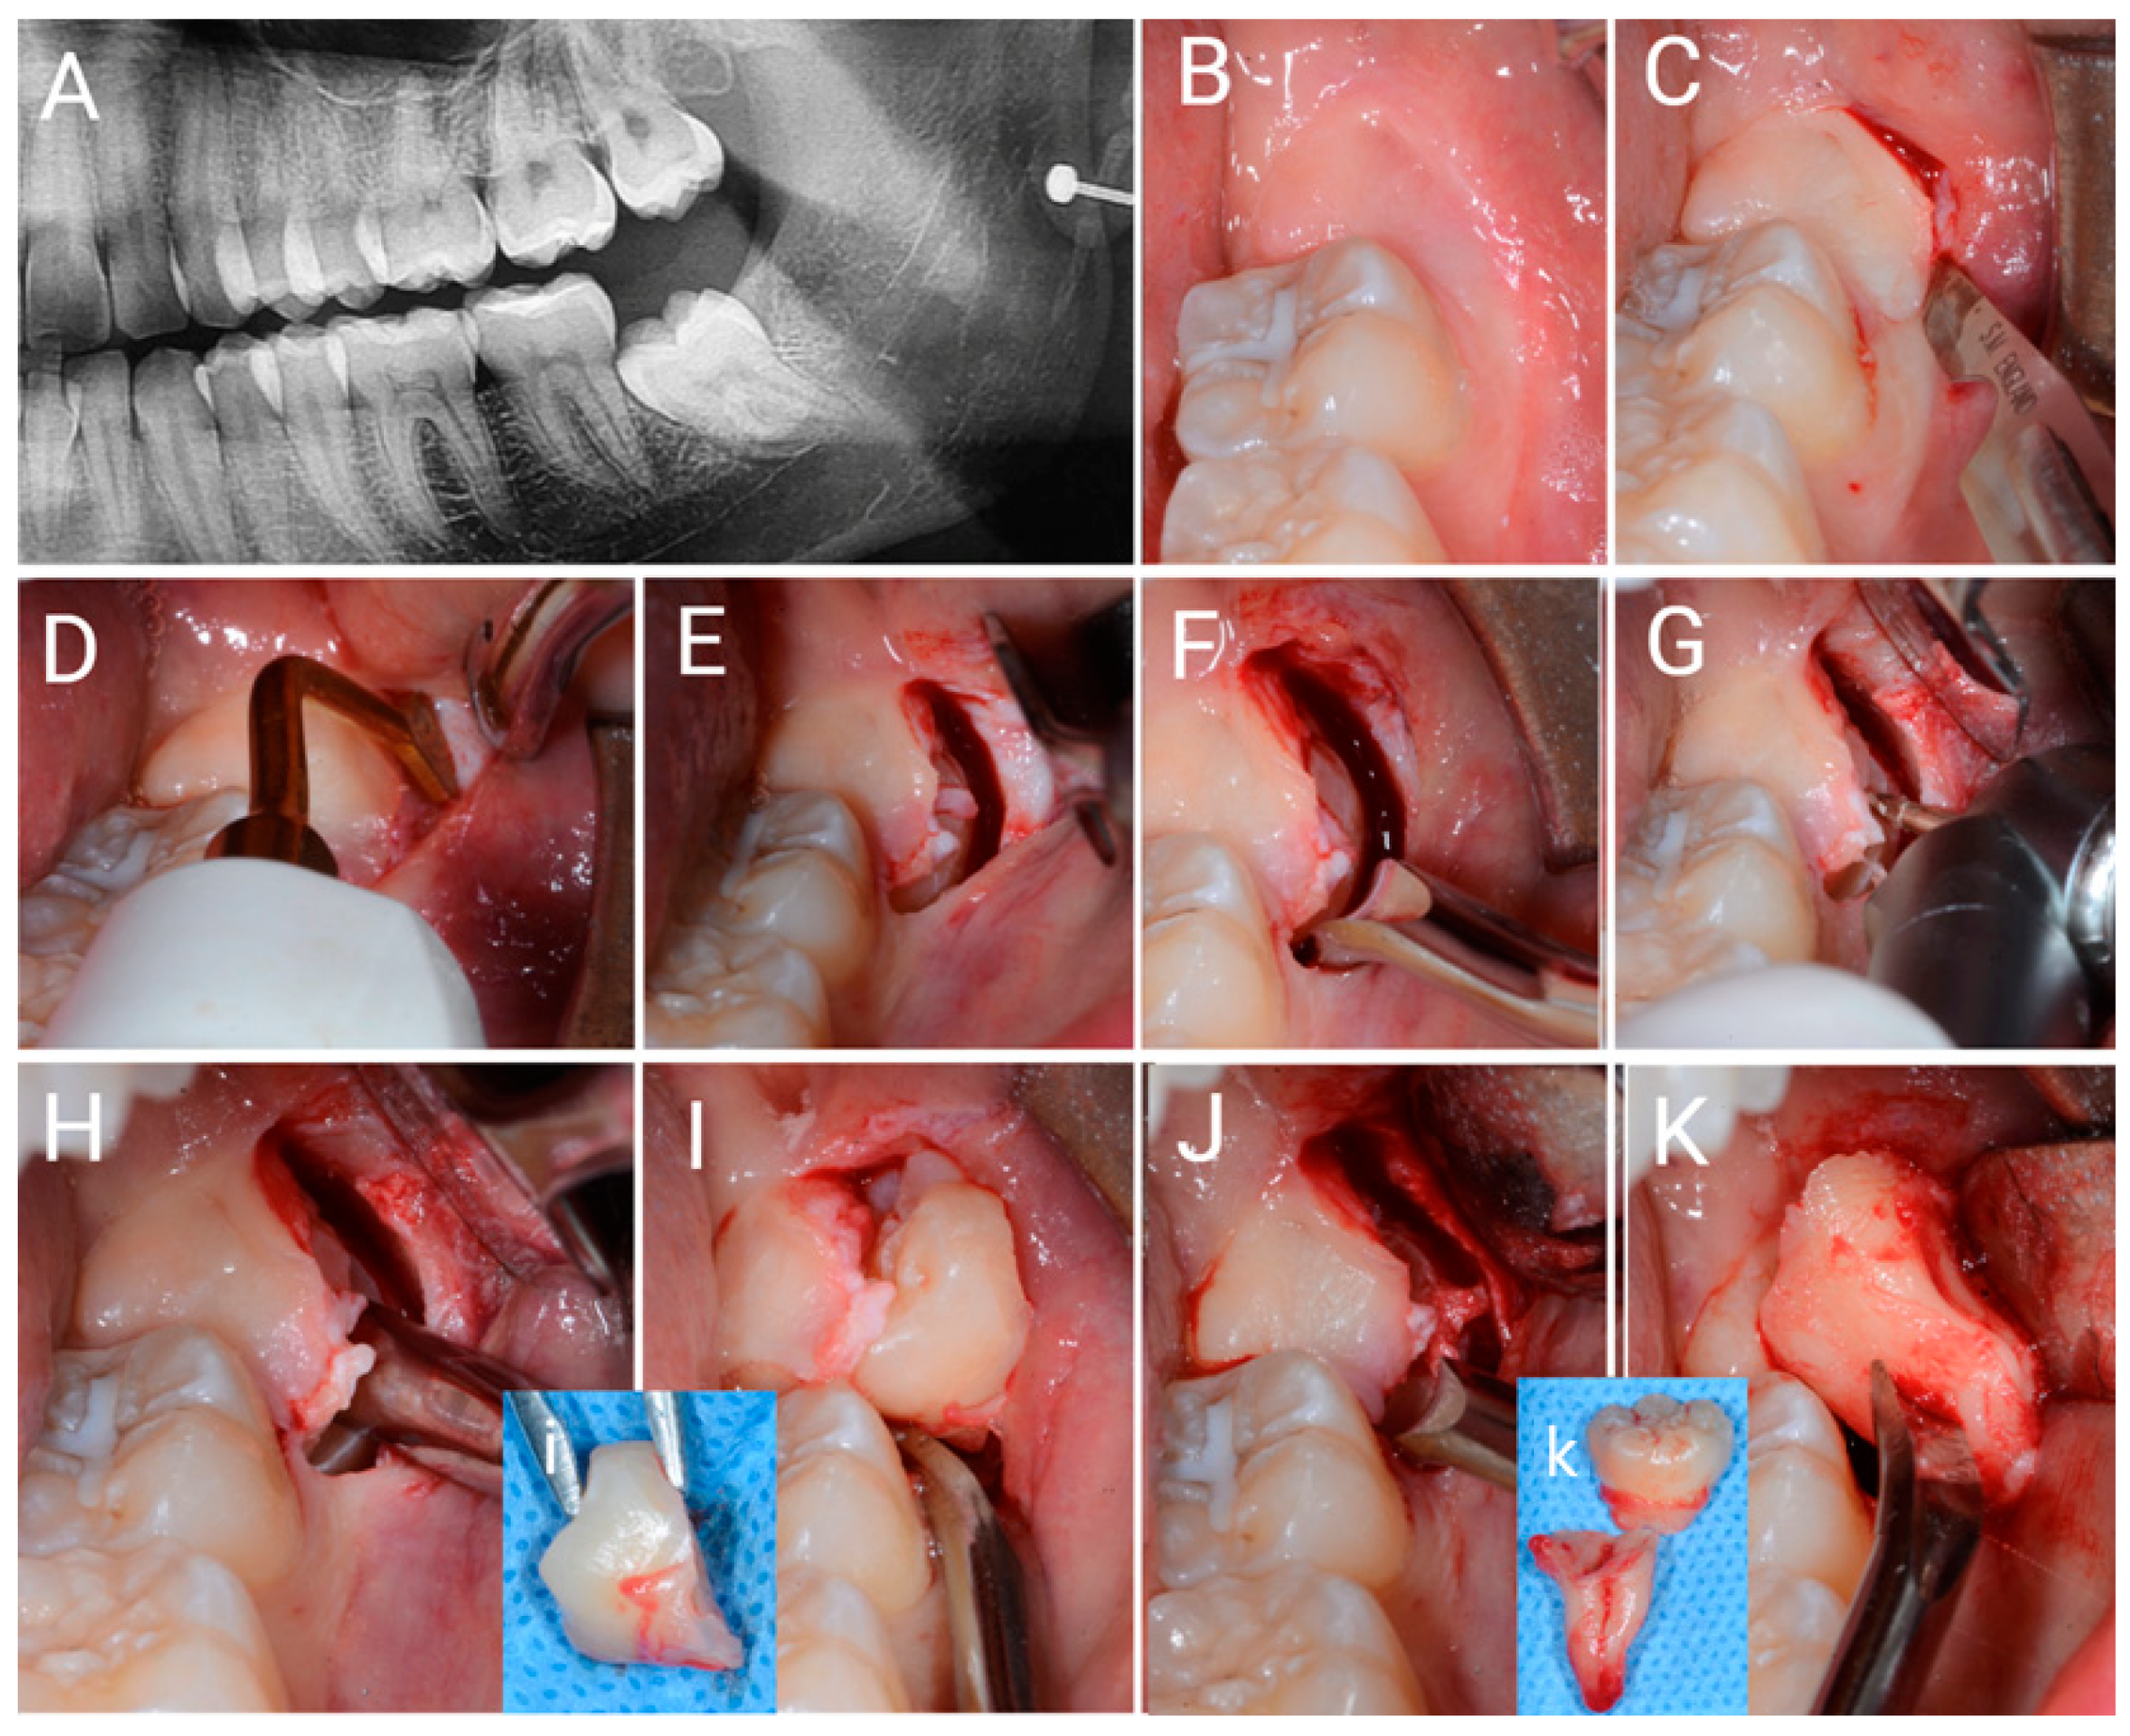

Figure 4. Images of surgery with single incision access (SIA). (A) OPT X-ray image of the impacted i3M. (B) Clinical view. (C) The single incision is performed in the soft buccal mucosa, where the next ostectomy will then be performed. (D) Ostectomy is performed with an OT6 piezosurgical instrument. (E) Ostectomy is performed through a single incision. (F) Early mobilization of the impacted tooth is achieved using a 31F elevator. (G) Odontotomy is performed using a surgical bur and a surgical air-rotor. (H) Part of the crown is fractured by rotating an elevator in the odontotomy slot. (I) Using the elevator, the first portion of the impacted tooth is removed through a single incision. (J) The remaining part of the impacted tooth is mobilized by the elevator. (K) The roots of the impacted tooth are removed. (i) = removed crown; (k) = two portions of the removed tooth.

The SIA surgery is an evolution of the FSA previously described [9]. Indeed, SIA surgery differs from FSA because only one incision is performed, and no soft tissue is removed (Figure 3C,D). The SIA procedure is shown in Figure 4B–M.

In detail a single incision is performed using a 15c blade (Swann-Morton Limited Owlerton Green, Sheffield, UK) beginning distobuccally of the second lower molar in the mucosa approximately 1 mm buccally to the attached gingiva, which can be found in the retromolar trine, drawing a semicircular line, which follows the next ostectomy form around the 3M crown.

The surgeon must already have a clear idea of where he will perform the ostectomy before seeing the impacted 3M. For this reason, the surgeon must properly analyse the X-ray examinations and palpate with his finger the soft tissues above the presumed position of the 3M crown, in order to obtain a clear idea of the regional anatomy. The above-described incision begins in the soft mucosa distobuccal to the second molar and describes a semicircle buccally, ending against the buccal surface of the second molar crown, approximately between the two buccal cuspids.

No flap is elevated, but the soft tissues are stretched through with the help of an 11 × 40 mm Langenbeck metal retractor (Stoma Dentalsysteme GmbH & Co KG, Emmingen-Liptingen, Germany) which is tightened buccally in the soft mucosa of the cheek and firmly pushed down. The incision is enlarged so that the surgeon can then perform the ostectomy through it. Protecting the buccal side of the incision with the help of a Prichard periosteal elevator (Prichard periosteal PPR36, Hu-Friedy Mfg. Co., Chicago, IL, USA), the ostectomy can be performed using a piezosurgical instrument with an appropriate tip OT6 (Mectron via Loreto 15A, 16042 Carasco (GE), Italy). The surgeon enters the bone and touches the enamel crown with the bur and, sliding against the crown, performs the correct ostectomy. Still through the incision, and now through the performed ostectomy, the surgeon can carry out a partial odontotomy using the same bur (H162 STZ Komet Lemgo, Germany) and airotor (NSK TI-MAX 45° Stand-Titan, NSK Dental, Kanuma, Japan). The odontotomy is completed by fracturing the residual portion of the tooth using 31F and 32F elevators (Hu-Friedy Mfg. Co., Chicago, IL, USA). With the help of a mini-Friedmann 90° rongeur (RMF90 rongeur Friedmann 90°, small cod RMF90, Hu-Friedy Mfg. Co., Chicago, IL, USA), the surgeon removes the fractured portion of the 3M through the same single incision. If necessary, further odontotomies can be performed instead of enlarging the incision. The roots and residual portions of the 3M are extracted through the incision with the help of 31F and 32F elevators (Hu-Friedy Mfg. Co., Chicago, IL, USA). To control the post-extraction socket, a 3 mm Lucas bone curette is used in the superficial portion, while avoiding deep penetration of the metal instrument into the apical region of the alveolus to prevent inadvertent damage to the inferior alveolar nerve. If present, the dental follicle is eliminated. The surgery ends without any type of suture, by waiting for the blood clot to stabilise.